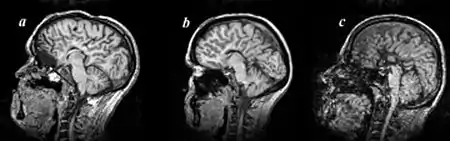

Callosal disorders can be diagnosed through brain imaging studies or during autopsy.[6] They may be diagnosed through an MRI, CT scan, Sonography, prenatal ultrasound, or prenatal MRI.[1]